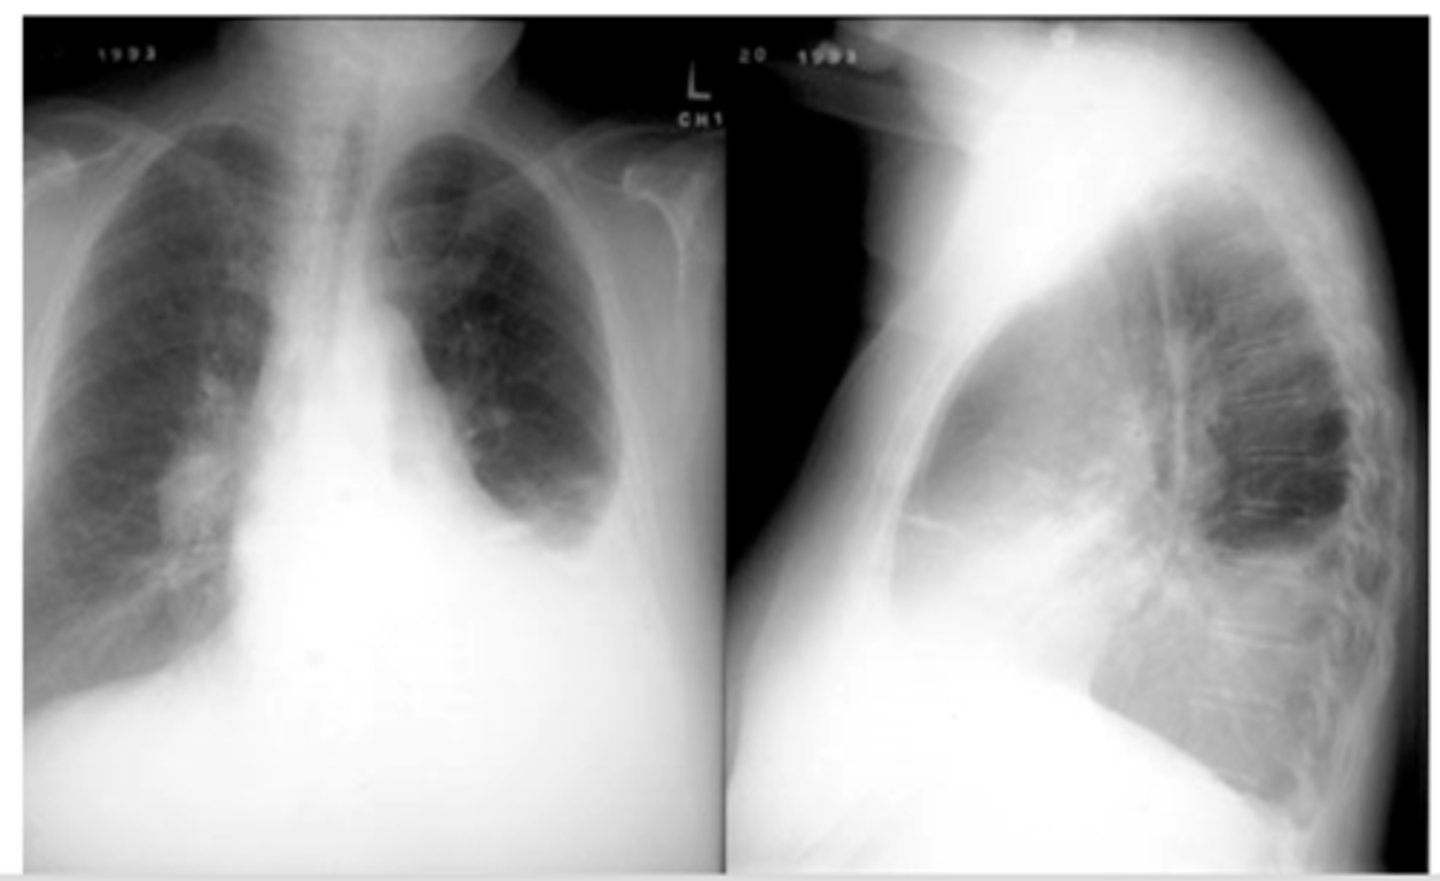

Often associated with COPD or emphysema but bullae can be present in normal asymptomatic patients. (this pt has emphysema)

-Flattening of hemidiaphragms with blunting of costophrenic angles.

-Increased AP diameter of chest on lateral view (barrel chest)

-Presence of bullae or large air cavities

Flattened diaphragms, ant mediastinal space increased --> COPD/emphysema

Dx and ID radiological findings